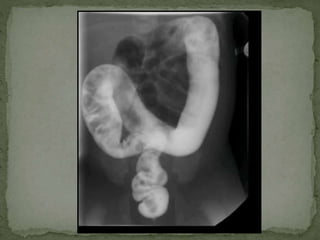

 Barium enema single contrast study- 18th June, 2013

 Moderate distension of large bowel without definite

haustral pattern

 May represent distal segment Hirschsprung disease

 Findings can also be seen in constipation and myxdema

 Barium enemasingle contrast study- 18th June, 2013  Moderate distension of large bowel without definite haustral pattern  May represent distal segment Hirschsprung disease  Findings can also be seen in constipation and myxdema